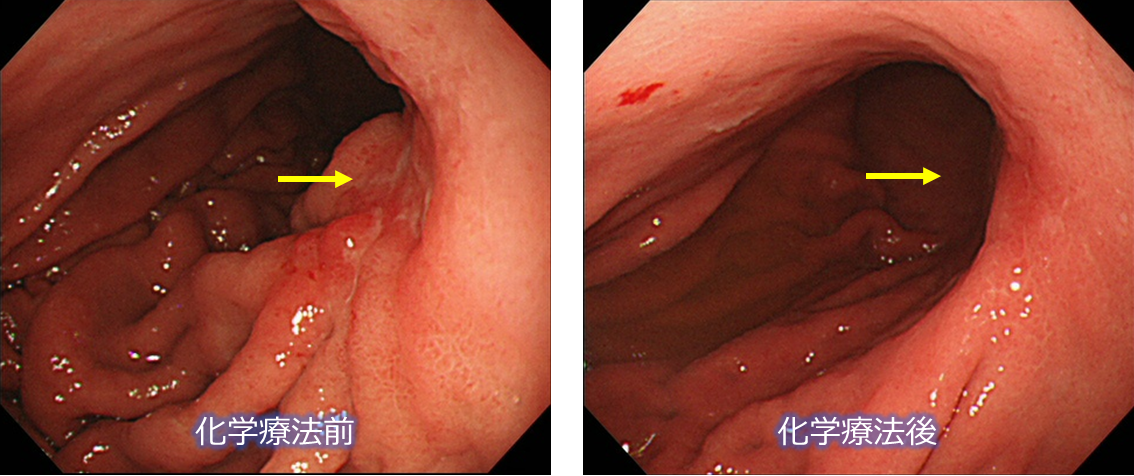

化学療法で消失したスキルス胃がん

化学療法で消失した潰瘍浸潤型胃がん